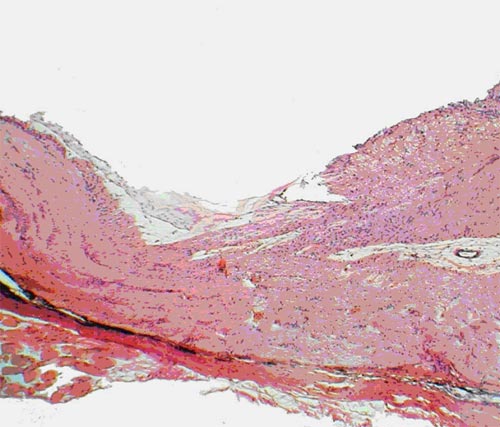

У группы интактных животных (№ 1) проведенные собственные исследования позволили выявить, что в назальной половине сетчатки глаза количество ганглиозных клеток на 20-30% больше, чем в височной половине. В этой группе в обеих половинах сетчатки в слое фоторецепторов и биполяров по направлению к углу задней камеры глаза наблюдалось уменьшение толщины слоев и количества клеток. Обнаружено, что количество крупных клеток в группе интактных животных больше при приближении к цилиарному телу, а мелких - к диску зрительного нерва. В группе интактных животных (№ 1) в ганглиозном слое располагались клетки с ядрами различных размеров. Цитоплазма клеток имела слабо эозинофильную окраску, ядра хорошо прокрашивались гематоксилином в синий цвет (рис. 1).

Интактные кролики. Обычное содержание клеток в сетчатке: 1 - ганглиозный слой, 2 - слой биполярных клеток. Окраска гематоксилином и эозином. Ув.  200

Рис. 1. Интактные кролики. Обычное содержание клеток в сетчатке: 1 - ганглиозный слой, 2 - слой биполярных клеток. Окраска гематоксилином и эозином. Ув. 200

Количество их распределялось следующим образом: всего клеток - 509,67±12,35, из них: мелких - 184,00±5,00; средних - 229,17±12,41; крупных - 96,50±3,58. В норме соотношение: мелкие/средние/ крупные клетки было 36/45/19%. Толщина слоя аксонов ганглиозных клеток при измерении на расстоянии 350 мкм от края решетчатой пластинки, где ход аксонов был еще параллельным сетчатке, равнялась 129,15±1,86 мкм. Слой имел равномерное слабо розовое окрашивание, на его поверхности лежали тонкостенные капилляры (рис. 2).

Интактные кролики. Толщина слоя аксонов ганглиозных клеток сетчатки у диска зрительного нерва. Окраска гематоксилином и эозином.  Ув.  200

Рис. 2. Интактные кролики. Толщина слоя аксонов ганглиозных клеток сетчатки у диска зрительного нерва. Окраска гематоксилином и эозином. Ув. 200